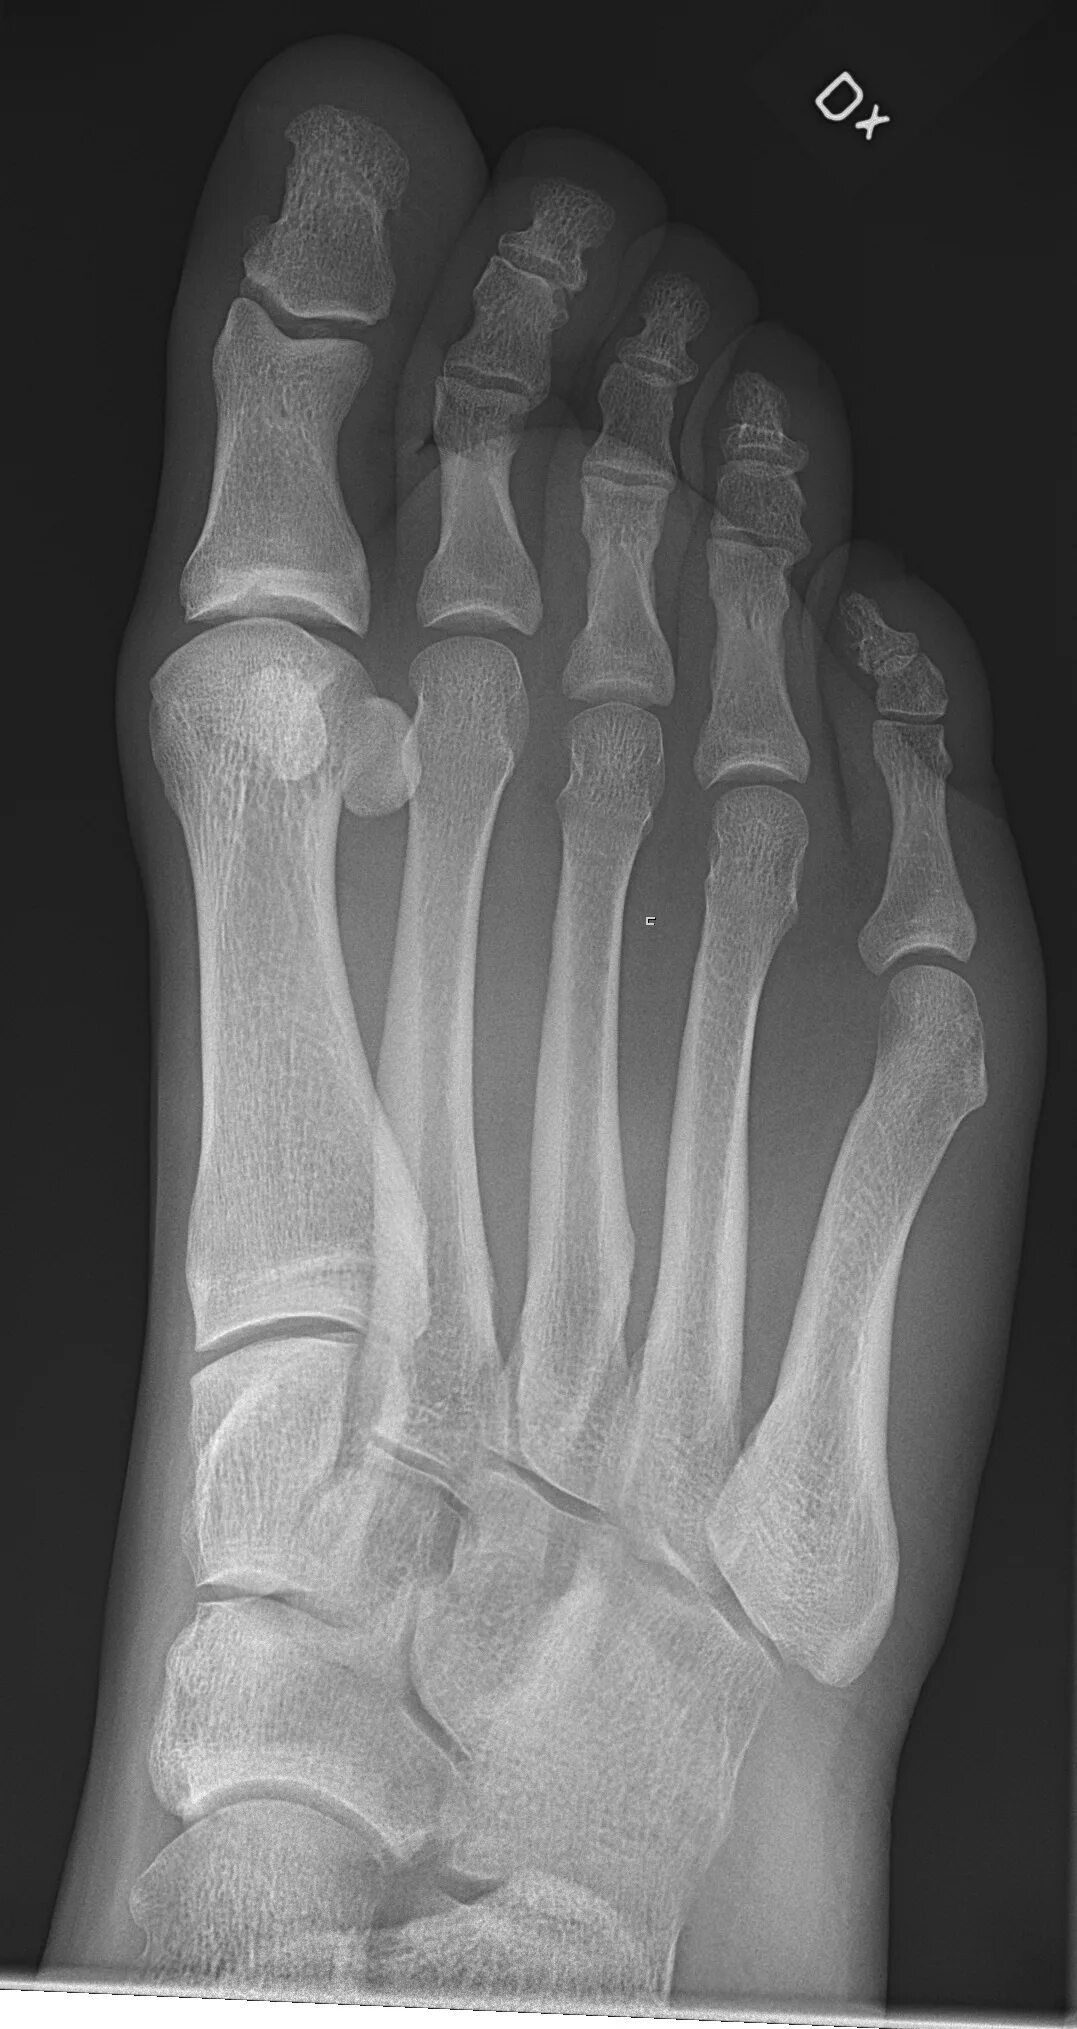

Source x rays